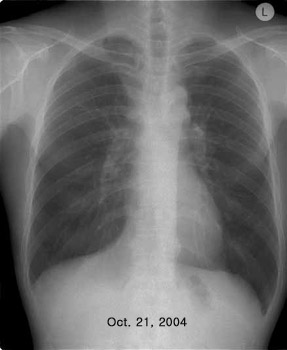

ÀÌÀü¿¡ °áÇÙ °ú°Å·Â ÀÖ´Â ³²ÀÚ 41¼¼·Î CXR ÀÌ»ó ¼Ò°ßÀ¸·Î refer